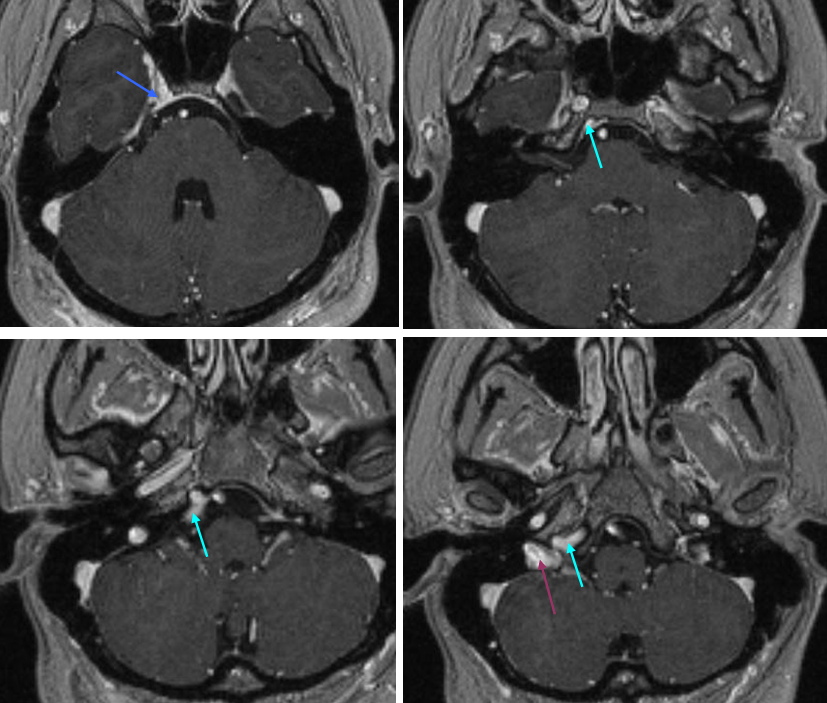

Анатомия внутренней яремной вены: КТ изображения